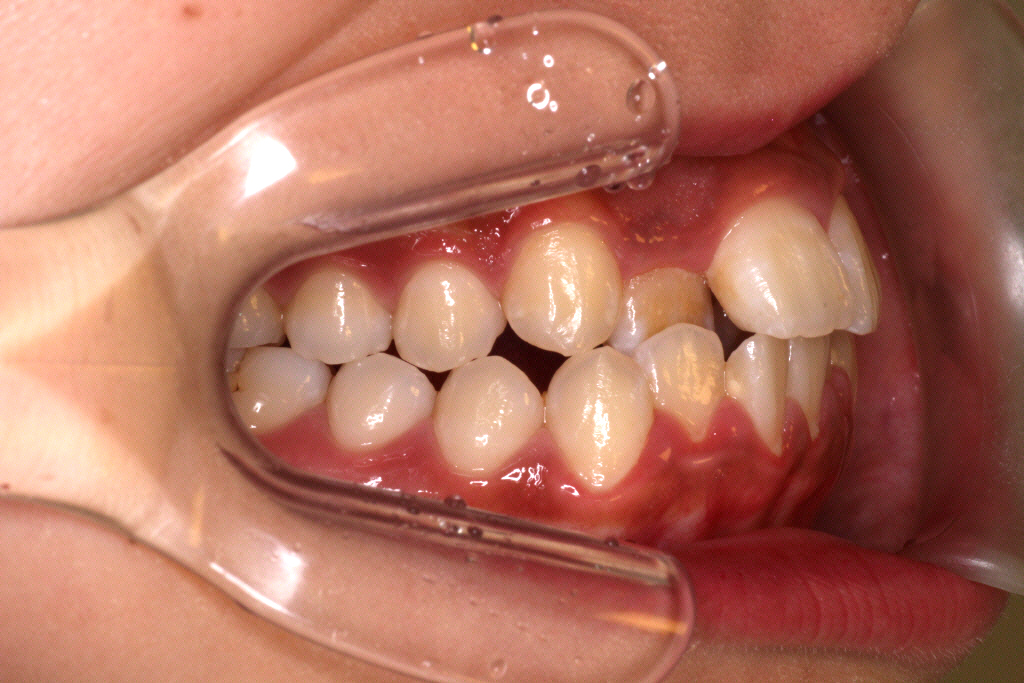

↓上下マウスピースを1週間ずつ使い、

51枚中27枚目くらいでマウスピースが合わなくなった9ヶ月後のお口の中の状態です。

患者さんの左上の1番目と3番目の間に隙間ができてきて、2番目の歯が少し見えるようになりました。

まだまだ並ばせていかないといけないので、リファイメント1回目(マウスピースの作り直し)を行いました。